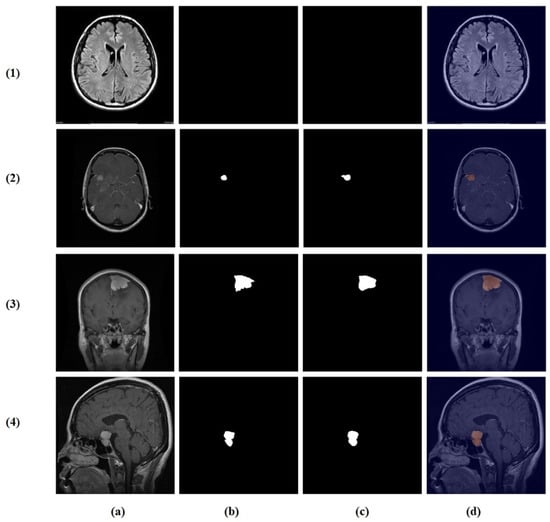

The brain tumor segmentation dataset from Kaggle [22] comprises 4237 T1-weighted contrast-enhanced MRI images (512 × 512 pixels) across the following four classes: no tumor (1595), glioma (650), meningioma (999), and pituitary tumor (994), with corresponding ground truth masks (Figure 2).

Figure 2.

Example cases from the brain tumor segmentation dataset: (1) original MRI slices and (2) corresponding ground truth masks. Columns (a–d) show the following four classes: no tumor, glioma, meningioma, and pituitary tumor.